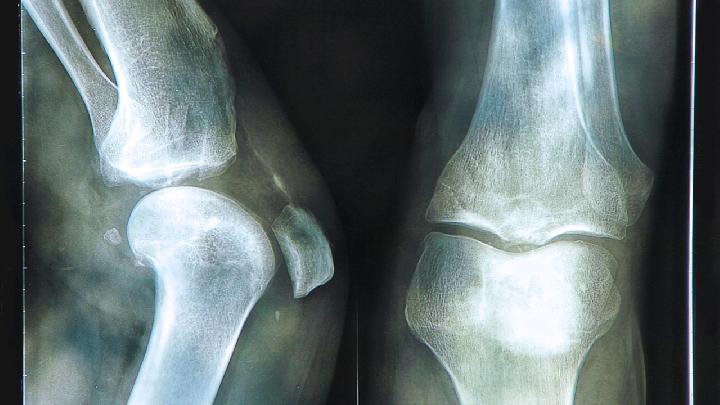

骨关节炎为一种退行性病变,系由于增龄、肥胖、劳损、创伤、关节先天性异常、关节畸形等诸多因素引起的关节软骨退化损伤、关节边缘和软骨下骨反应性增生,又称骨关节病、退行性关节炎。那么,骨关节炎有什么特点呢?

骨关节炎是骨科常见的一种疾病,是中老年人群中发病率比较高的一种疾病,应该注意引起重视,骨关节炎是一种慢性疾病,病程也常常是反复发作了,早期的诊断是非常重要的,有助于患者及时开展治疗,早期患者的主要症状就是出现疼痛,那么具体骨关节炎的诊断方法有哪些呢?

骨关节炎是常见的骨科疾病,也是一种慢性疾病,目前临床的数据显示,我国的中老年人群中骨关节炎的发病率是极高的,患者的生活还有工作也是受到了比较严重的影响,应该注意及时进行治疗,在治疗之前,我们要检查确诊,那么骨关节炎如何检查呢?请看下文的介绍: